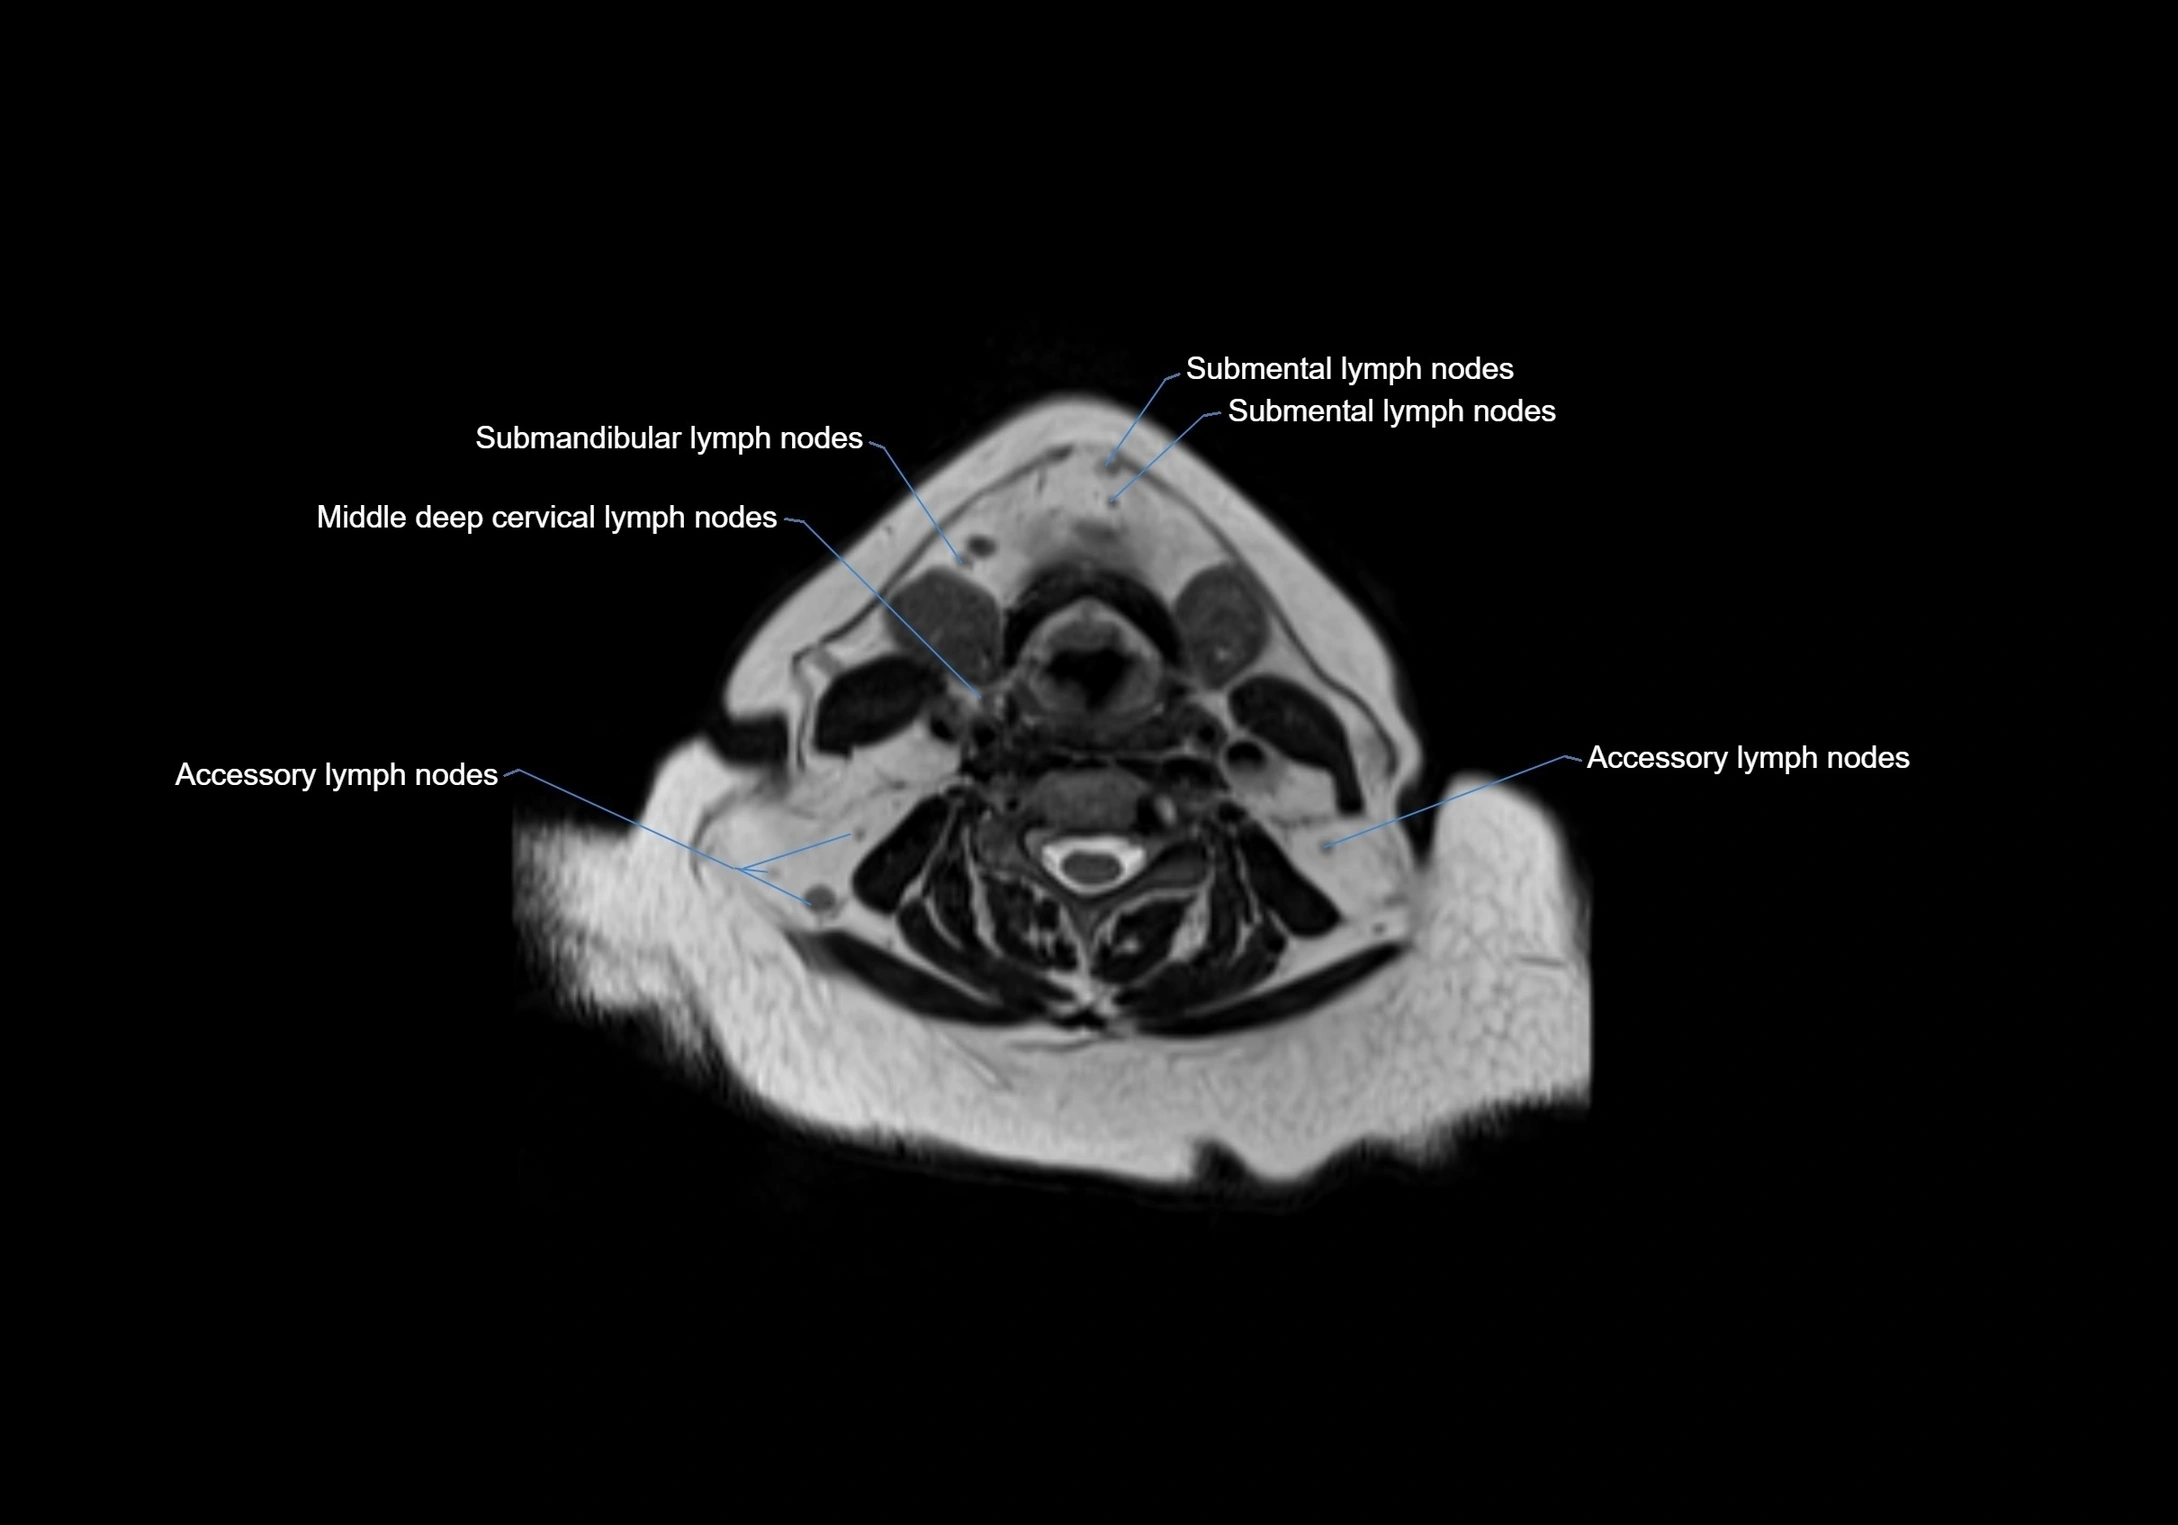

Location

• Found along primary lymph node chains, including preauricular, submandibular, parotid, and occipital regions

• Embedded in subcutaneous fat or superficial fascia, often lateral or posterior to primary nodes

• Variable in number; may occur unilaterally or bilaterally, depending on individual anatomy

MRI Appearance

T1-weighted images:

• Normal accessory nodes appear as small, oval hypointense to intermediate signal structures within subcutaneous fat

• Surrounded by hyperintense fat, enhancing contrast for visualization

• Pathological nodes may appear enlarged or rounded, sometimes with cortical thickening

MRI images

image